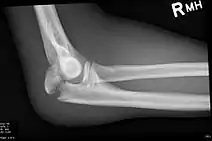

Olecranon fracture

To assess an olecranon fracture, a careful skin exam is performed to ensure there is no open fracture. Then a complete neurological exam of the upper limb should be documented.[5][2] Frontal and lateral X-ray views of the elbow are typically done to investigate the possibility of an olecranon fracture.[1] A true lateral x-ray is essential to determine the fracture pattern, degree of displacement, comminution, and the degree of articular involvement.